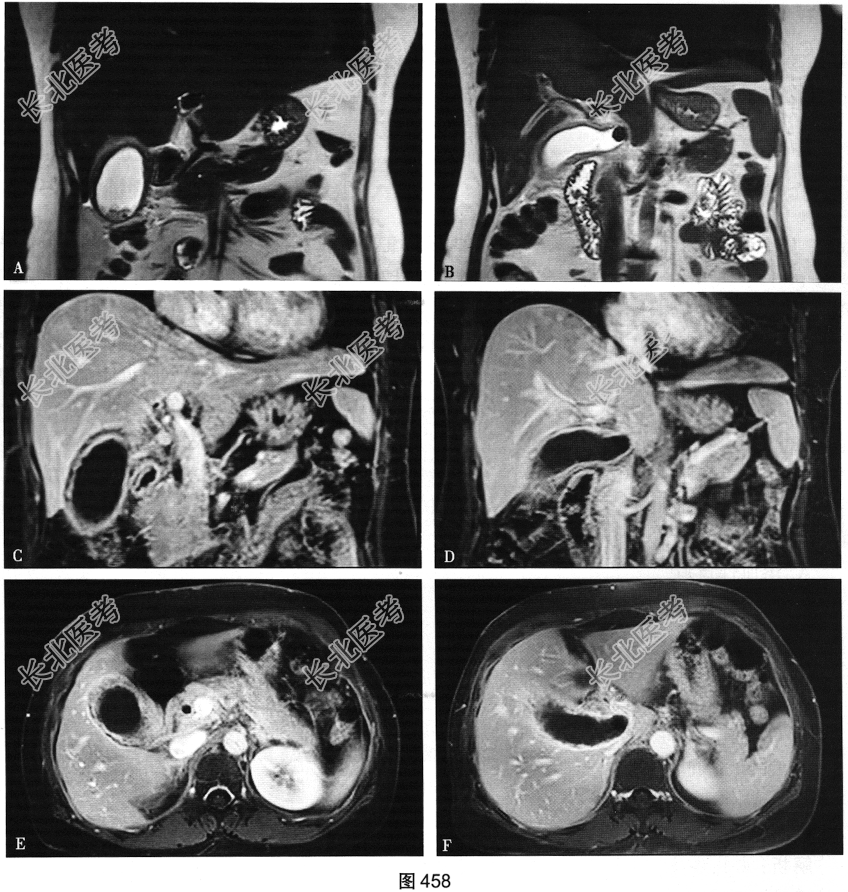

- 多项选择题4.[提示]患者行急诊超声检查发现异常,进一步行腹部增强MRI检查, 如图458所示。根据患者以上检查结果,考虑可能的诊断是( )

A、胆总管结石

B、肝脓肿

C、胆囊结石

D、肝内胆管结石

E、急性胰腺炎

F、急性胆囊炎

G、急性胆管炎

H、急性腹膜炎

I、肾结石

J、输尿管结石

K、胃肠道穿孔

关注下方微信公众号,搜题查看答案

- 多项选择题5.从患者病史和MRI图像推测,该患者急性发作伴感染表现的可能原因是( )

A、暴饮暴食

B、胆囊结构先天畸形

C、胆总管结石嵌顿

D、腹膜炎累及

E、肝内外胆管结构变异

F、大量饮酒

G、胆囊颈部结石嵌顿